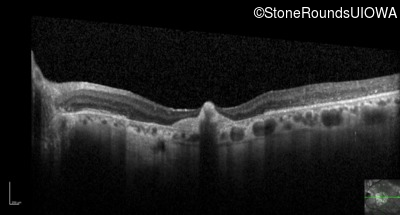

Optical Coherence Tomography - Right - 20/125 -2

Exemplar / OCT Stack